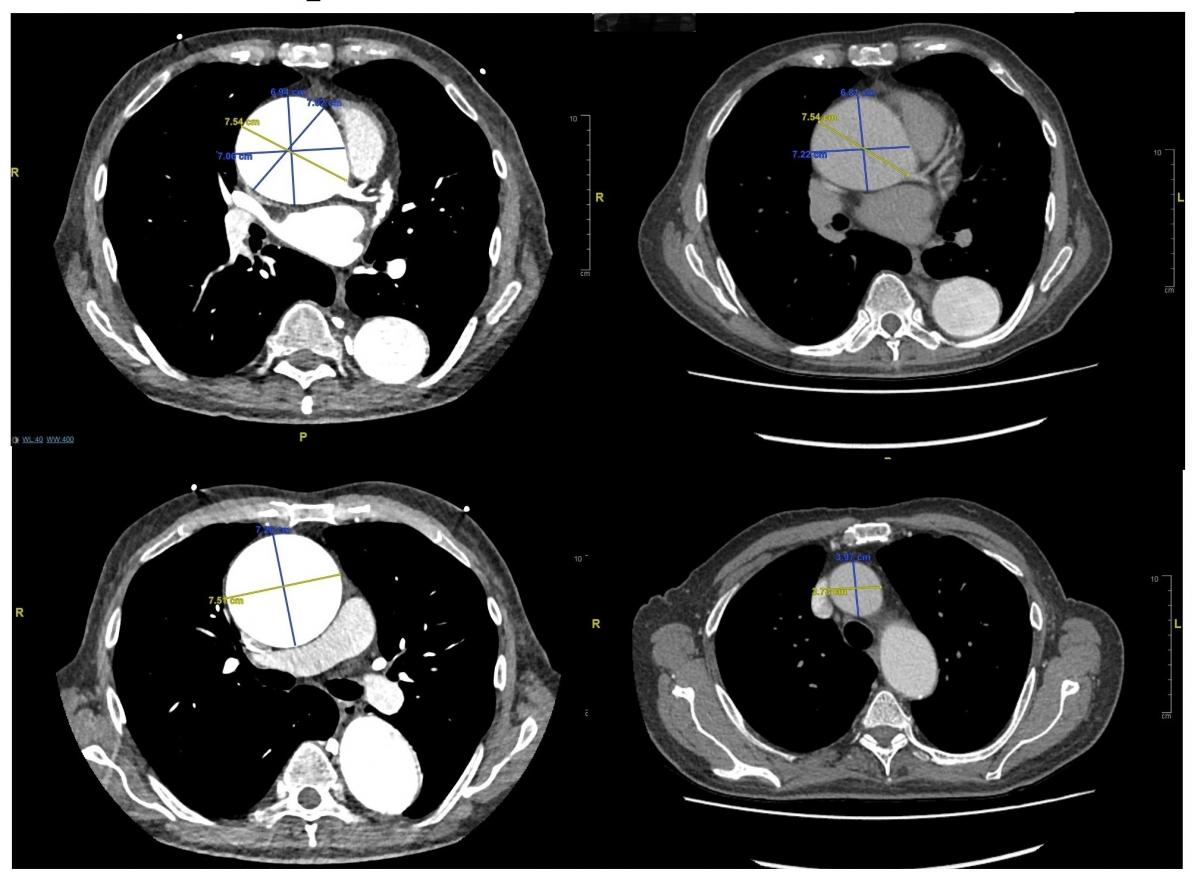

The patient in this video was a 73-year-old man who presented with acute abdomen; he later underwent appendectomy. During the abdominal investigation, he had a CT scan (Figure 1) and transthoracic echocardiogram.

These tests showed that his ascending aorta and root were dilated up to 75 mm with severe aortic valve regurgitation, and his ejection fraction was 50%. His additive EuroSCORE was 11. Cumulative bypass time was 195 minutes, cumulative cross clamp-time was 142 minutes, and total circulatory arrest time was 32 minutes. He was admitted one day before the operation and was discharged on the seventh postoperative day with very good recovery.